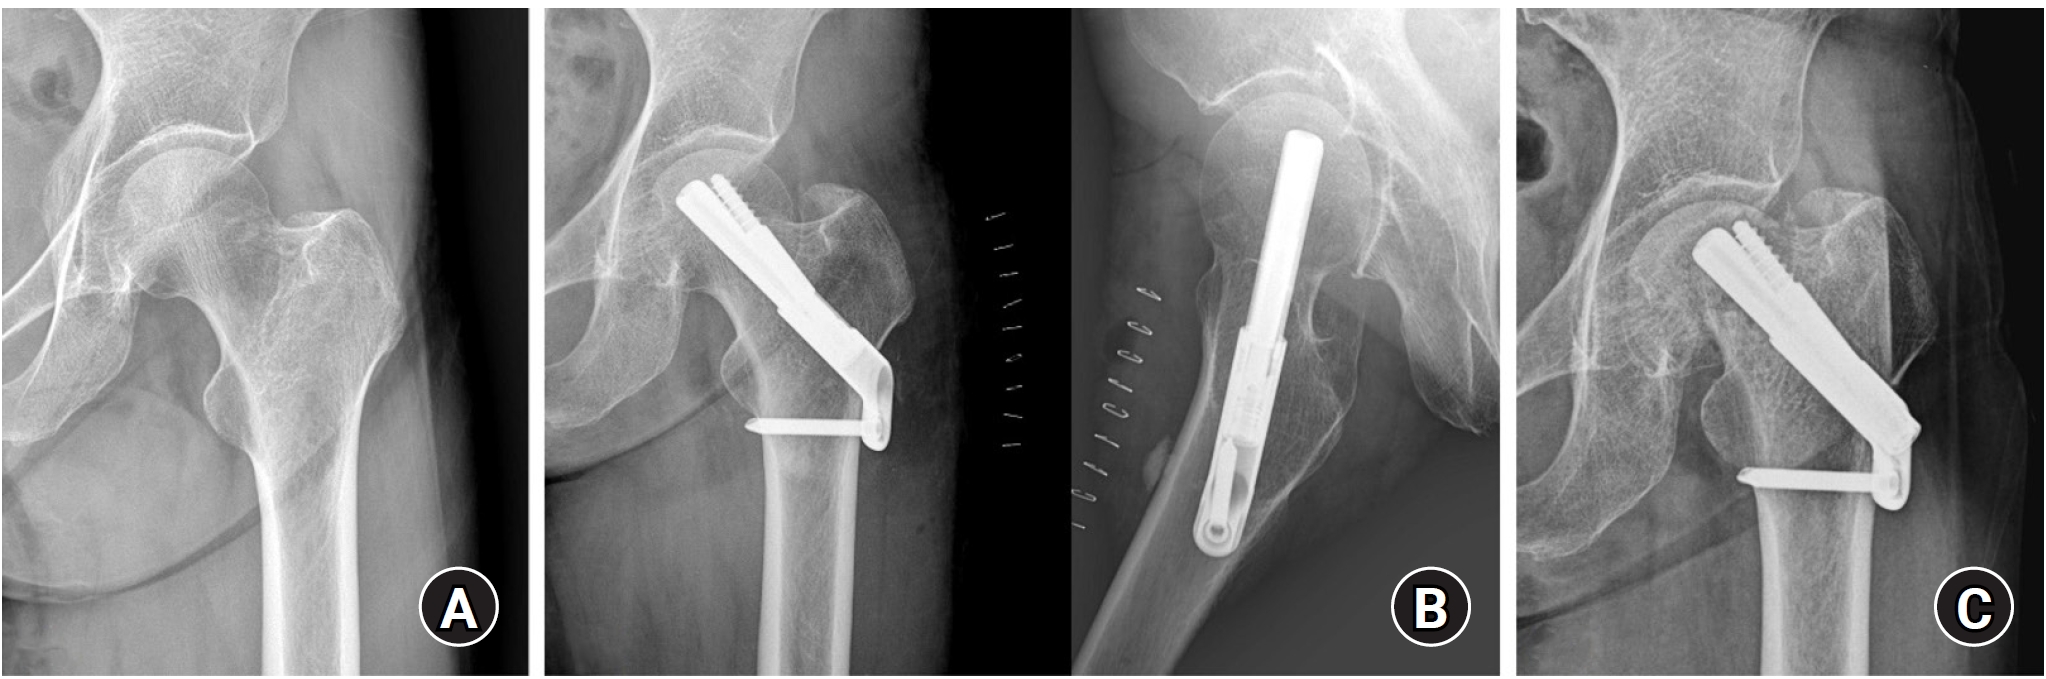

Radiological outcomes

At the final follow-up, the union rate was 87.5% (21/24) in the FNS group and 95.8% (23/24) in the DHS group, with no statistically significant difference between the two groups (P=0.296) (Figs. 2, 3). The mean femoral neck shortening was measured at 6.1 mm in the FNS group and 5.9 mm in the DHS group, and no significant difference was observed (P=0.427).

Fig. 2.

(A, B) A 67-year-old female patient with a right femoral neck fracture (Garden type 1) treated with the femoral neck system. (C) The postoperative 4-year radiograph shows a well-healed fracture site and no complications related to the implant. Femoral neck shortening (D2‒D1) was calculated as the difference in the distance from the center of the femoral head to the lateral cortex of the femur between the immediate postoperative and final follow-up radiographs.

Fig. 2. (A, B) A 67-year-old female patient with a right femoral neck fracture (Garden type 1) treated with the femoral neck system. (C) The postoperative 4-year radiograph shows a well-healed fracture site and no complications related to the implant. Femoral neck shortening (D2‒D1) was calculated as the difference in the distance from the center of the femoral head to the lateral cortex of the femur between the immediate postoperative and final follow-up radiographs.